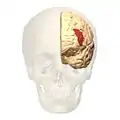

Brodmann area 46

Brodmann area 46, or BA46, is part of the frontal cortex in the human brain. It is between BA10 and BA45.

BA46 is known as middle frontal area 46. In the human brain it occupies approximately the middle third of the middle frontal gyrus and the most rostral portion of the inferior frontal gyrus. Brodmann area 46 roughly corresponds with the dorsolateral prefrontal cortex (DLPFC), although the borders of area 46 are based on cytoarchitecture rather than function. The DLPFC also encompasses part of granular frontal area 9, directly adjacent on the dorsal surface of the cortex.

Frontal view.